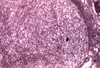

What is shown here?

FSGS

have adhesions called synechiae- focal lesions on top (in purple) but the rest looks okay